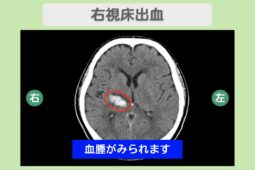

動脈硬化

動脈硬化は加齢や高血圧、糖尿病などが要因となり、血管壁がもろくなる疾患で、脳梗塞のリスクが高いです。

もろくなった血管壁を修復するために、血小板が凝集し血栓ができやすくなります。

動脈硬化が進行し、体のどこかで作られた血栓が脳血管まで到達したり、脳内で血栓ができた場合は、脳梗塞を発症する可能性があります。